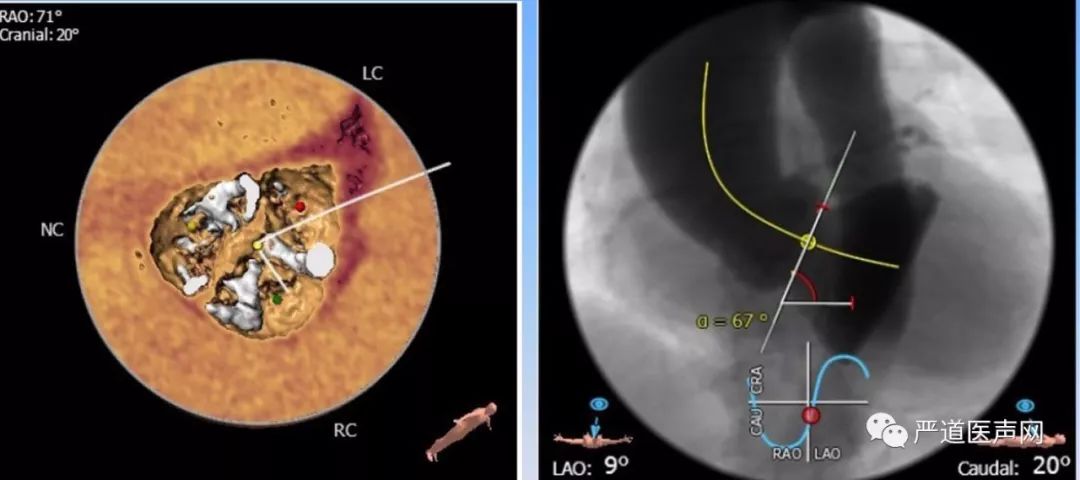

主动脉瓣瓣环直径 29.7*23.7 mm,瓣环周长84.6mm,面积557.5mm2,主动脉窦部直径32.1mm*30.6mm*35.2mm,左心室流出道周长89.6mm,面积584.5mm2。(如下图)

左侧冠脉开口高度较低9.0mm,右侧冠脉开口14.5mm。(如下图)

CTA提示患者瓣膜重度钙化,Type I型二叶主动脉瓣,横位心,主动脉与左心室夹角67°。(如下图)